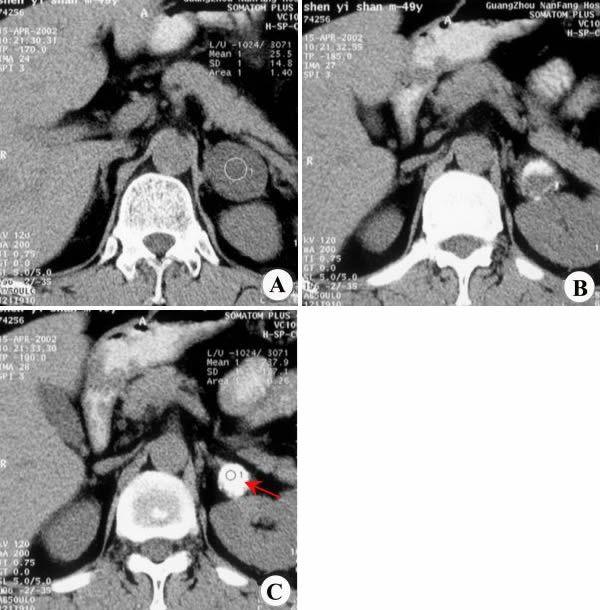

CT左肾上腺囊肿合并钙化

左肾上腺囊肿合并钙化CT图

影像表现:CT平扫(A~C)示左侧肾上腺可见一类圆形均匀稍低密度影,壁薄,边界清晰,内有团块状钙化影(C,↑)。